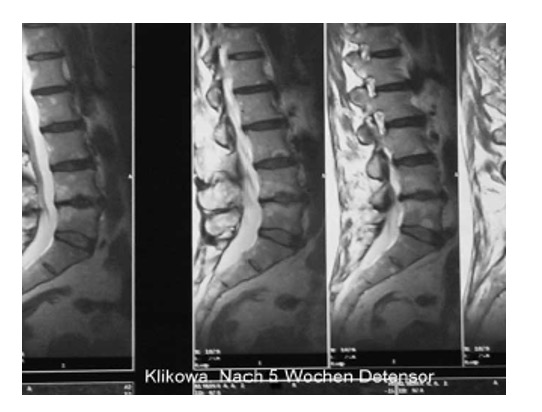

Эффективность лечения оценивалась по данным клинического наблюдения, показаниям электрофизиологических исследований: рентгенографии (включая рентгенографическую компьютерную томографию и магнитно-резонансную томографию (рис. 21а, 21б, 22а, 22б)), параметрам функции внешнего дыхания, показателям гемодинамики при реоэнцефалографии и лазерной допплерографии, компьютерно-оптической топографии позвоночника, электроэнцефалографии, результатам измерения величины электрокожного сопротивления в репрезентативных точках акупунктуры, стабилометрии и др. У всех пациентов независимо от основной патологии при мануальном обследовании выявлены функциональные блокады ПДС, напряжение различных групп мышц (прежде всего в мышцах верхнего плечевого пояса) и наличие в них болевых точек. Выраженность болевого синдрома оценивали по визуально-аналоговой шкале (ВАШ), выраженность тревожной и депрессивной симптоматики определяли по шкале А. Бека.

Рис. 21. Компьютерная томограмма поясничного отдела позвоночника при болевом синдроме

а) ДО проведения Детензор-терапии (отмечается заднецентральная грыжа межпозвонкового диска L4-L5 с компрессией дурального мешка и пролапс межпозвонкового диска на уровне L5-S1)

б) ПОСЛЕ проведения Детензор-терапии (отмечается регресс грыжи и пролапса межпозвонковых дисков)